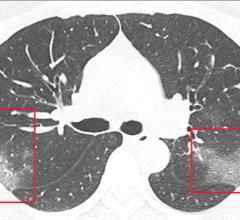

As the 2019-nCoV Pneumonia is taking the world by storm, researchers have found a possible way to predict this virus…

February 11, 2020 — The Radiological Society of North America (RSNA) journal Radiology has published a study from…